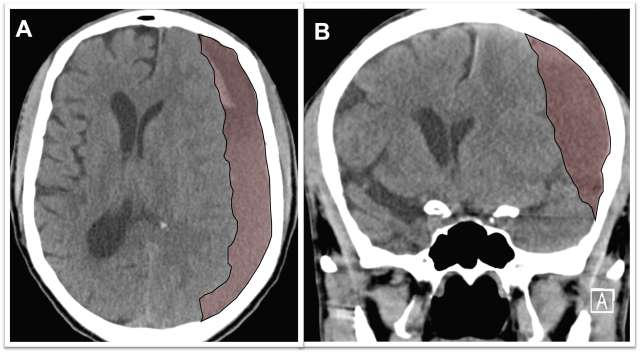

Chronic subdural hematoma (cSDH) is a collection of degrading blood products in the space between the surface of the brain and the inner lining of the skull, called the “dura mater.” These types of collections occur more frequently in older age groups due to the increased space between the brain surface and the dura mater as we age. Chronic subdural hematoma collections are thought to begin as relatively small bleeds after a minor event such as bumping of the head, but over time, the collections can grow, particularly in patients who have other reasons to bleed such as use of blood thinners or other medical reasons. If they become large enough, they create pressure on the brain and result in symptoms (Figure 1).

Middle Meningeal Artery Embolization – This procedure is performed in an endovascular suite with the patient asleep under general anesthesia. The endovascular surgeon uses minimally invasive technique to enter the blood vessels in the arm or leg and then advances small tubes called catheters through the arteries under x-ray guidance to the middle meningeal artery on the side of the subdural hematoma. The middle meningeal artery is located on the underside of the skull (outside of the brain) but also provides blood supply to the abnormal membranes that surround the hematoma and contribute to hematoma growth (Figure 2). Under fluoroscopic guidance, the surgeon delivers a specially made liquid glue material (called nBCA or Onyx) or small particles through the small tube and permanently blocks the middle meningeal artery. Platinum micro-coils can be used as well. After the procedure, the tubes are removed and the small puncture site in the arm or leg artery is closed. In the weeks following the procedure, there is reduced bleeding from the subdural hematoma membranes and the hematoma collection slowly shrinks in size and often goes away completely over the course of several months (Figure 3).